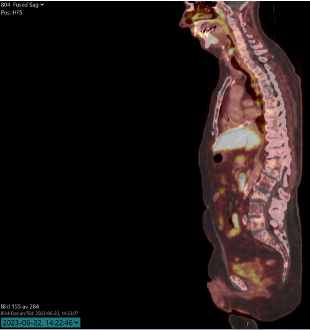

Efter det senast uppmätta PSA-värdet på 0,51 µg/l utförs en PSMA-PET som visar utbredda sklerotiska förändringar I skelettet samt små fokala upptag I bäckenet, sklerotiska förändringar, även något I kotpelaren men I övrigt inget I thorax/buk.